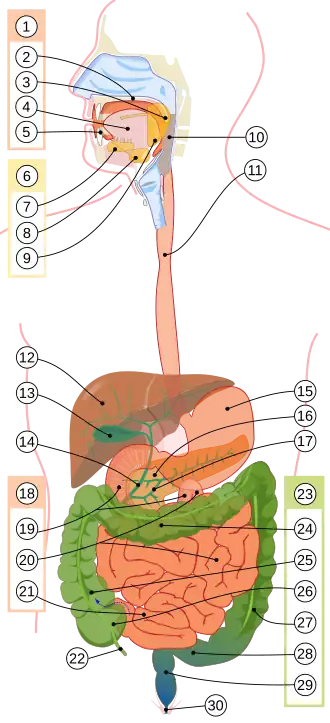

Желудочно-кишечный тракт человека

Пищевари́тельный, или желу́дочно-кише́чный тракт (ЖКТ) — система органов у человека, предназначенная для переработки и извлечения из пищи питательных веществ, всасывания их в кровь и лимфу и выделения из организма непереваренных остатков. Является частью пищеварительной системы человека[1].

В среднем длина пищеварительного канала взрослого мужчины составляет 5 метров ; в нём выделяются следующие отделы:

- Рот, или ротовая полость с зубами, языком и слюнными железами.

- Глотка.

- Пищевод.

- Желудок.

- Тонкая кишка, включая подотделы:

- Толстая кишка, включая подотделы:

- слепая кишка с червеобразным отростком,

- ободочная кишка со своими подотделами:

- прямая кишка с широкой частью — ампулой прямой кишки, и дистальной, нижней частью — заднепроходным каналом с анальным отверстием.